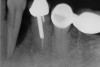

Figure 1  Tooth No. 5 showing advanced periodontal bone loss and a widened periodontal ligament space.

Figure 1

Figure 2  Same case as in Figure 1 after 1.5 years with no treatment. At that time, the bone loss affected the adjacent teeth. The apical extent of the bone loss was approximately 5 mm from the sinus floor.

Figure 2

To meet the needs of the new paradigm, treatment techniques have evolved for bone preservation. Figure 1 shows a case in which tooth No. 5 had advanced bone loss and the treatment option was to save it. The patient did not opt to have this treated, however. Figure 2 shows the same area approximately 18 months later when the advanced bone loss was also affecting the adjacent teeth. Traditional treatment—extraction of this tooth—would have led to a significant hard- and soft-tissue defect. Use of the alternative treatment—grafting of the socket at the time of extraction19,20—preserved the hard and soft tissue (Figure 3 and Figure 4). Grafting the socket to minimize postextraction ridge shrinkage is a much more conservative approach than performing ridge augmentation after extraction,21 which would have been required if the socket grafting had not been done in conjunction with the extraction.